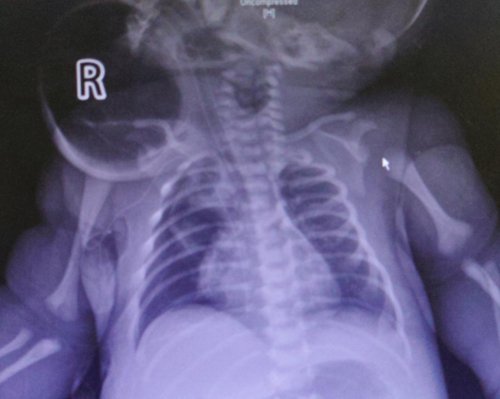

患儿为38+3周,出生体重为3.50 kg。孕检发现颈部肿物,出生后转入山大二院新生儿科。患儿颈部肿物进行性增大,逐渐出现呼吸困难并进行性加重,予气管插管呼吸机辅助通气。同时行胸片、胸部CT及颈部MRI提示右颈部见一巨大囊性异常信号灶,病灶最大截面约7.2cm*6.3cm,内见多水平分隔,对周围气管等组织造成压迫并导致移位;同时还存在纵膈气肿,双肺炎症。

文章插图